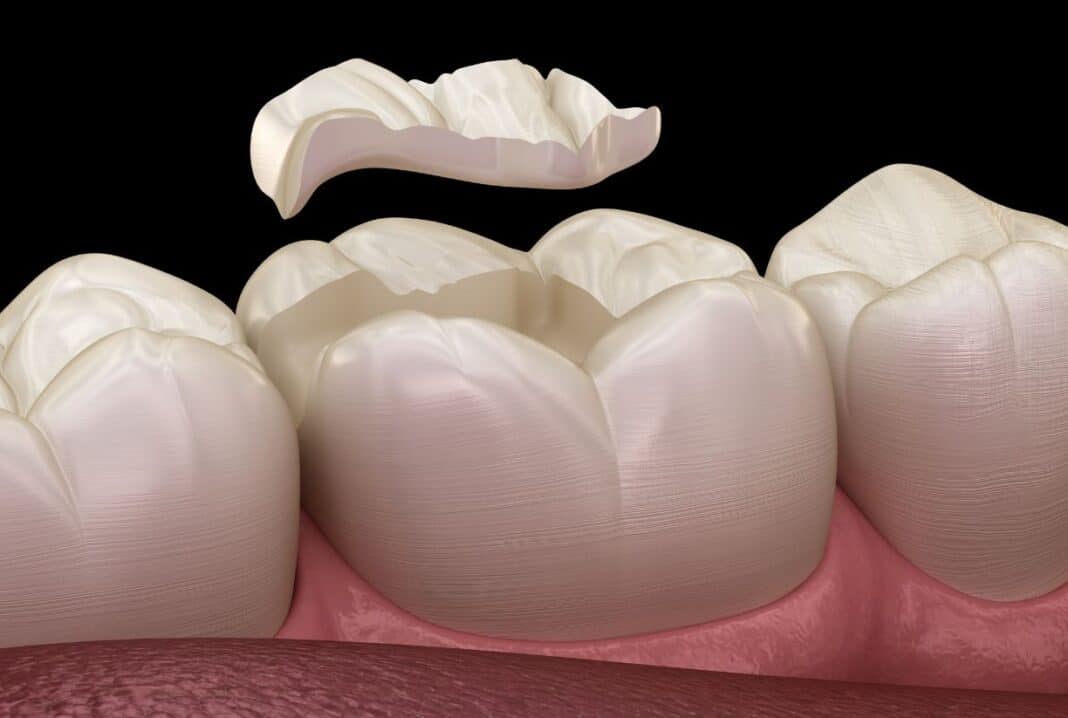

Ένθετα και επένθετα

Είναι σφραγίσματα από πορσελάνη ή ρητίνη που κατασκευάζονται από τον τεχνίτη. Ο οδοντίατρος τροχίζει το δόντι όπως στο σφράγισμα και αντί να βάλει στην κοιλότητα σύνθετη ρητίνη (άσπρο σφράγισμα) ή αμάλγαμα παίρνει αποτύπωμα και ο οδοντοτεχνίτης κάνει το σφράγισμα.

Τα ένθετα και τα επένθετα έχουν πολύ καλύτερη αισθητική, μεγαλύτερη αντοχή, όποτε και πολύ μεγαλύτερη διάρκεια ζωής.